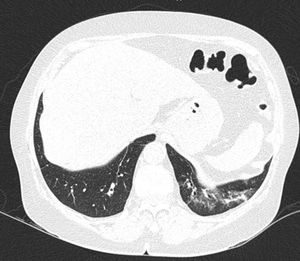

In ILD, there is a decrease in acoustic impedance between the lung air and the soft tissues of the chest wall, because part of the space initially occupied by air volume is replaced by infiltration of inflammatory cells or connective tissue, leading to pleural line disturbances and vertical artefacts called "B-lines". B-lines are indicative of increased subpleural lung density prior to consolidation and may be caused by the presence, not exclusively, of interstitial disease.25 The pleural line becomes irregular and thickened and may appear blurred and fragmented. B-lines are shown as vertical hyperechoic streak-like artefacts arising from the pleural line and extending to the end of the screen without fading, blurring the A-lines, and moving synchronously with the pleural sliding. The presence of multiple B-lines is the defining ultrasound sign of "interstitial syndrome".26Fig. 2 shows a CT scan of a patient with RA and ILD; Fig. 3 shows the ultrasound findings.